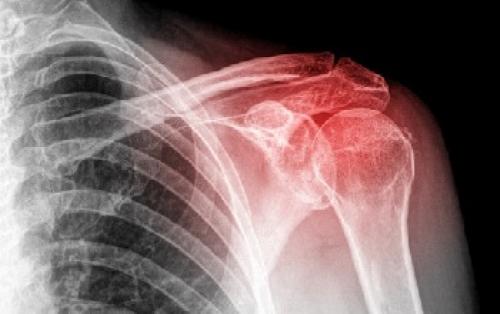

Боль и хруст в плечевом суставе, как правило, являются клиническим признаком некоторых заболеваний. Остановимся на этих патологиях и характерной для них симптоматике подробнее:

- Суставная нестабильность — возникает в результате чрезмерно интенсивных физических нагрузок, при которых особенному давлению подвергается плечелопаточный сустав. Данной проблеме наиболее подвержены профессиональные спортсмены, гимнасты, лица, чья работа связана с поднятием тяжестей (например, грузчики).

- Травмирование плеча и мышечных тканей. При этом болезненная симптоматика и хруст проявляются спустя несколько суток после травмы и носят постоянный или временный характер, что зависит от особенностей травматического повреждения.

- Артриты — воспалительный недуг, поражающий суставы. Данному заболеванию сопутствует специфический хрустящий звук, сильный болевой синдром, ограничения двигательной подвижности в области поражения.

- Остеохондроз — похрустывание в плечевом суставе выступает в качестве одного из симптомов остеохондроза шейного отдела позвоночного столба. Заболевание сопровождает ярко выраженный болевой синдром и значительное ограничение двигательной активности. Степень проявления болезненной симптоматики зависит от стадии течения патологического процесса и величины давления, оказываемого на нервные корешки.

- Артрозы — данному заболеванию сопутствует болезненность суставов и ограниченность их подвижности, в силу образования специфических разрастаний, именуемых остеофитами.

- Отложение солей — весьма распространенная причина появления неприятного хруста в области плечевого сустава. Спровоцировать данное нарушение могут разные факторы, к наиболее распространенным из них принято относить нерациональное питание, избыточный вес (ожирение), злоупотребление алкогольными напитками, малоподвижность, почечную недостаточность.

- Бурсит и тендиниты — это воспалительный процесс, затрагивающий сухожилия и непосредственно область плечевого сустава. Спровоцировать возникновение данной патологии могут такие факторы, как инфекции, ревматические заболевания, травмирование, чрезмерные физические нагрузки.